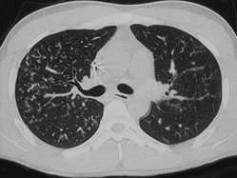

问题 男,26岁,发热,夜间盗汗,咳嗽半月余,请结合CT检查选出最可能的诊断 ( )

选项 A、肺转移瘤 B、矽肺 C、间质性肺炎 D、弥漫型肺癌 E、粟粒型肺结核

答案 E